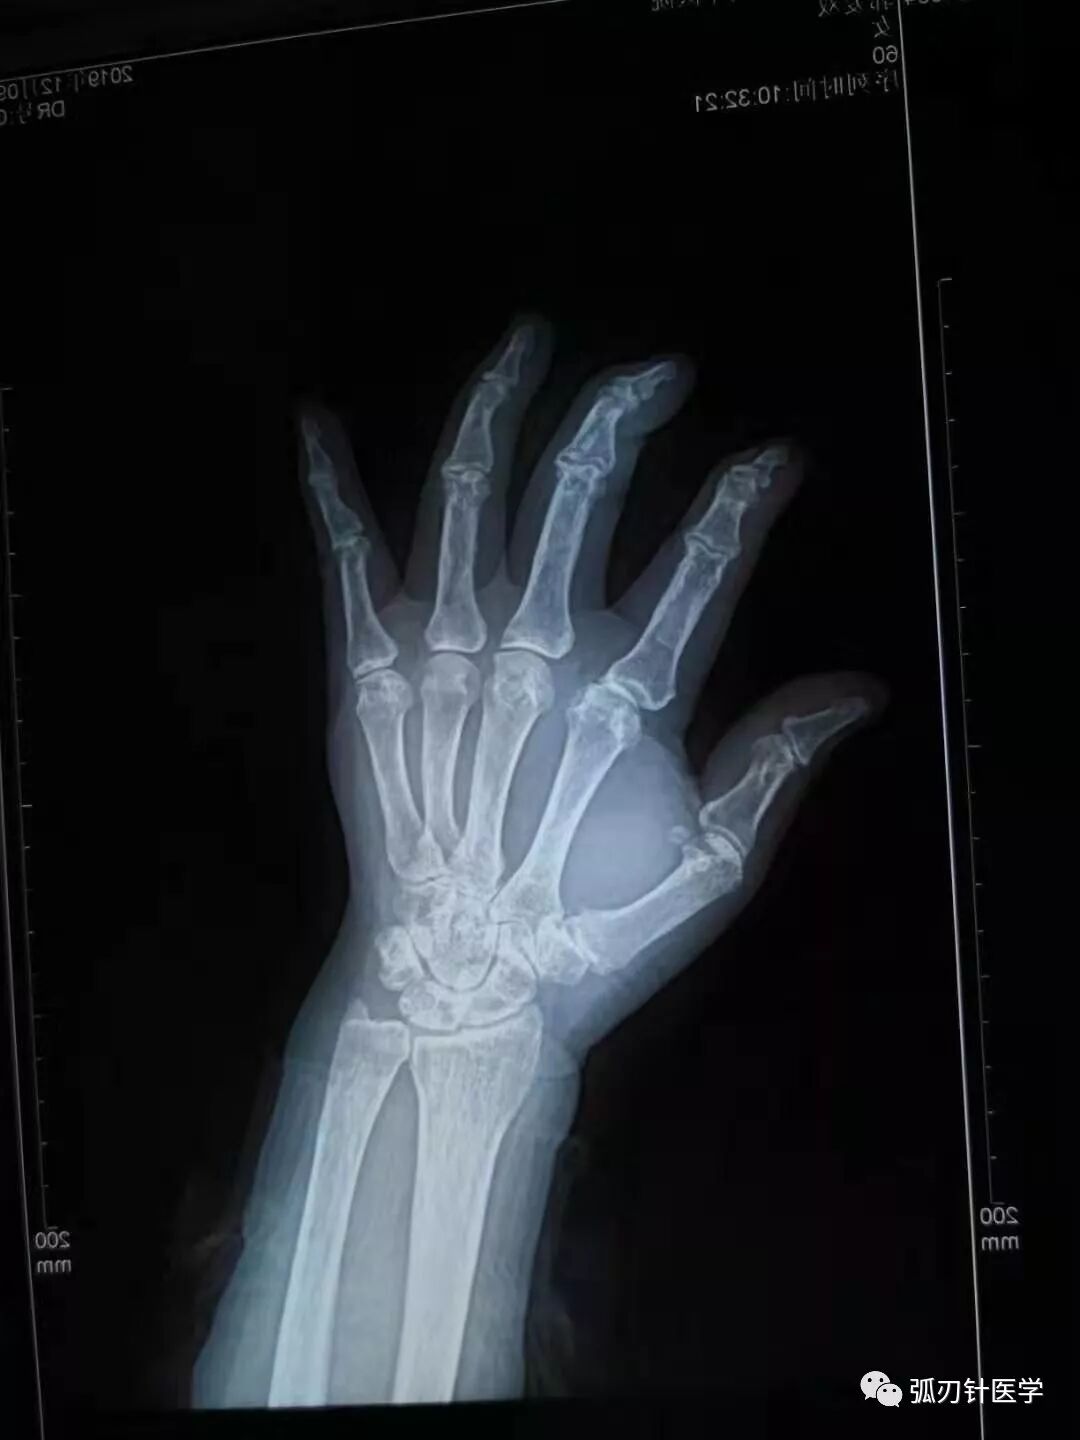

摘要: 右腕疼痛,考虑右手第一腕掌关节骨关节炎,不是腱鞘炎!猜你喜欢的文章一篇文章让你了解弧刃针技术全面学习弧刃针技术!12月12--15日第59期颈肩腰腿痛培训十合一精华班!弧刃针专题班(含解剖培训)12月12--14日郑州 ...

右腕疼痛,考虑右手第一腕掌关节骨关节炎,不是腱鞘炎!